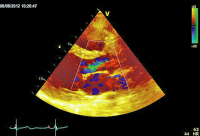

Parasternaler Querschnitt

Abbildung 3: Parasternaler Querschnitt der Aortenklappe mit Farbdoppler: Geringgradige Aorteninsuffizienz mit schmalem Jet.